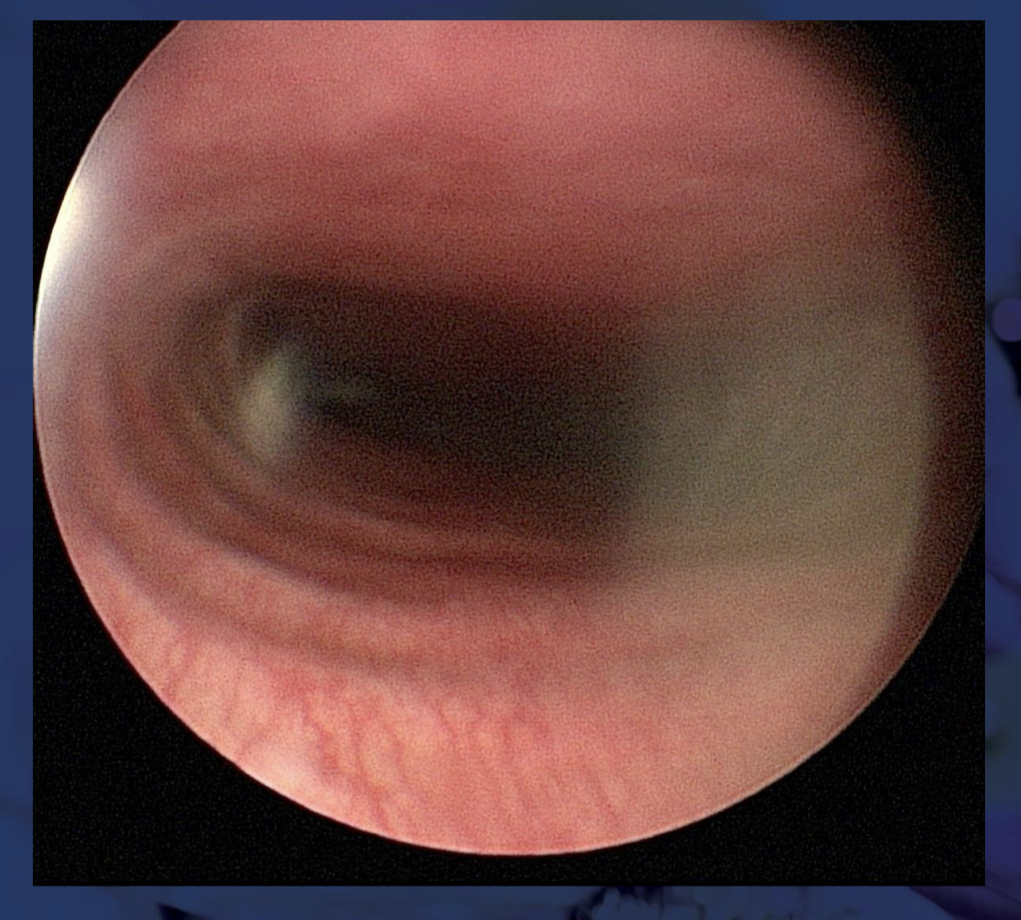

53

Laryngeal paralysis, laryngoscopy:

52

How can false negative diagnoses of laryngeal paralysis in patients with paradoxical arytenoid movement be avoided?

- light propofol - assistant indicates the inspiratory phase to the clinician (should abduct with inspiration) - Doxapram can stimulate respiration